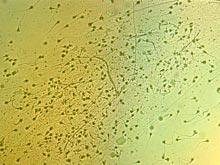

Исследователи подошли вплотную к созданию революционного контрацептива

Как отмечает The Daily Mail, в основе лежит открытие биологического механизма, работающего в сперматозоидах. Ученые обнаружили белок ABHD2, который дает сперматозоидам энергию для движения в сторону яйцеклетки и прорыва в нее. Итак, ABHD2 заставляет хвост...